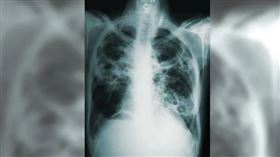

遠離肺阻塞從戒菸開始!

慢性阻塞性肺病(簡稱肺阻塞,COPD)過去被視為單一...

台大醫院內科部副主任王鶴健醫師說明,肺阻塞為慢性呼吸...

「咳痰悶喘」逾2週 恐這致命病警訊

肺阻塞常見症狀是咳嗽、氣喘、胸悶、有痰,經常會被當作...

致命肺阻塞別當感冒!這3症狀要注意

「咳、痰、喘」是肺阻塞典型症狀,但卻容易和氣喘、感冒...